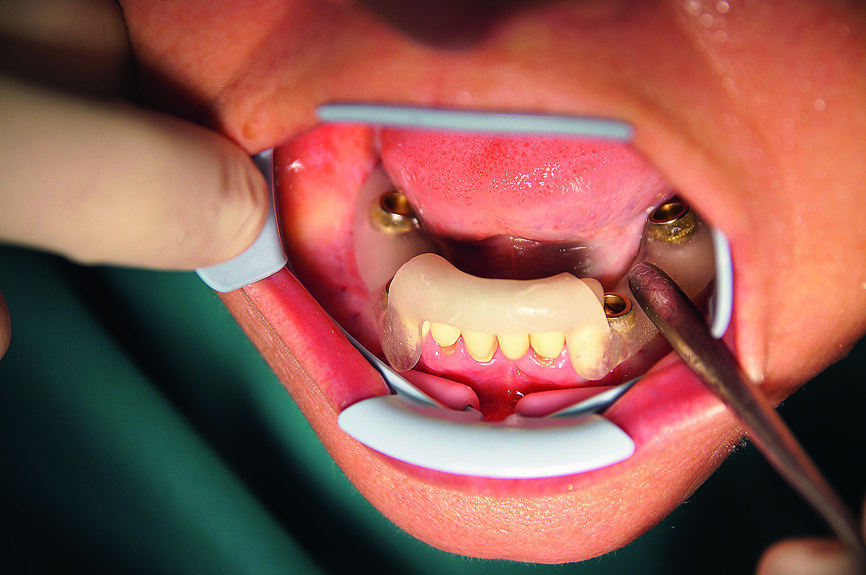

Fig. 18 : Tous les implants CAMLOG guidés dans la mandibule.

19 : Résultat de l’implantation avec tous les implants in situ.

L’insertion des implants a été réalisée à l’aide de la clé à cliquet DRM et de la douille standard, avec un couple de serrage d’environ 35–45 Ncm, afin de parvenir à une stabilité primaire maximale (Fig. 17). Par la suite, les tenons pour navigation implantaire et le guide chirurgical ont été retirés du maxillaire pour y insérer les façonneurs gingivaux, avec un couple de serrage de 25 Ncm (Figs. 18 et 19). Une technique similaire a été utilisée pour la préparation des lits implantaires et l’insertion des implants dans la mandibule, ou six implants CAMLOG de 4,3 mm in diamètre et de 11,0 mm de longueur ont été insérés sous guidage total dans les sites dentaires 15, 14, 12, 22, 24 et 25. Une tomographie panoramique dentaire postopératoire a permis de visualiser les implants insérés dans le maxillaire et la mandibule (Fig. 20).